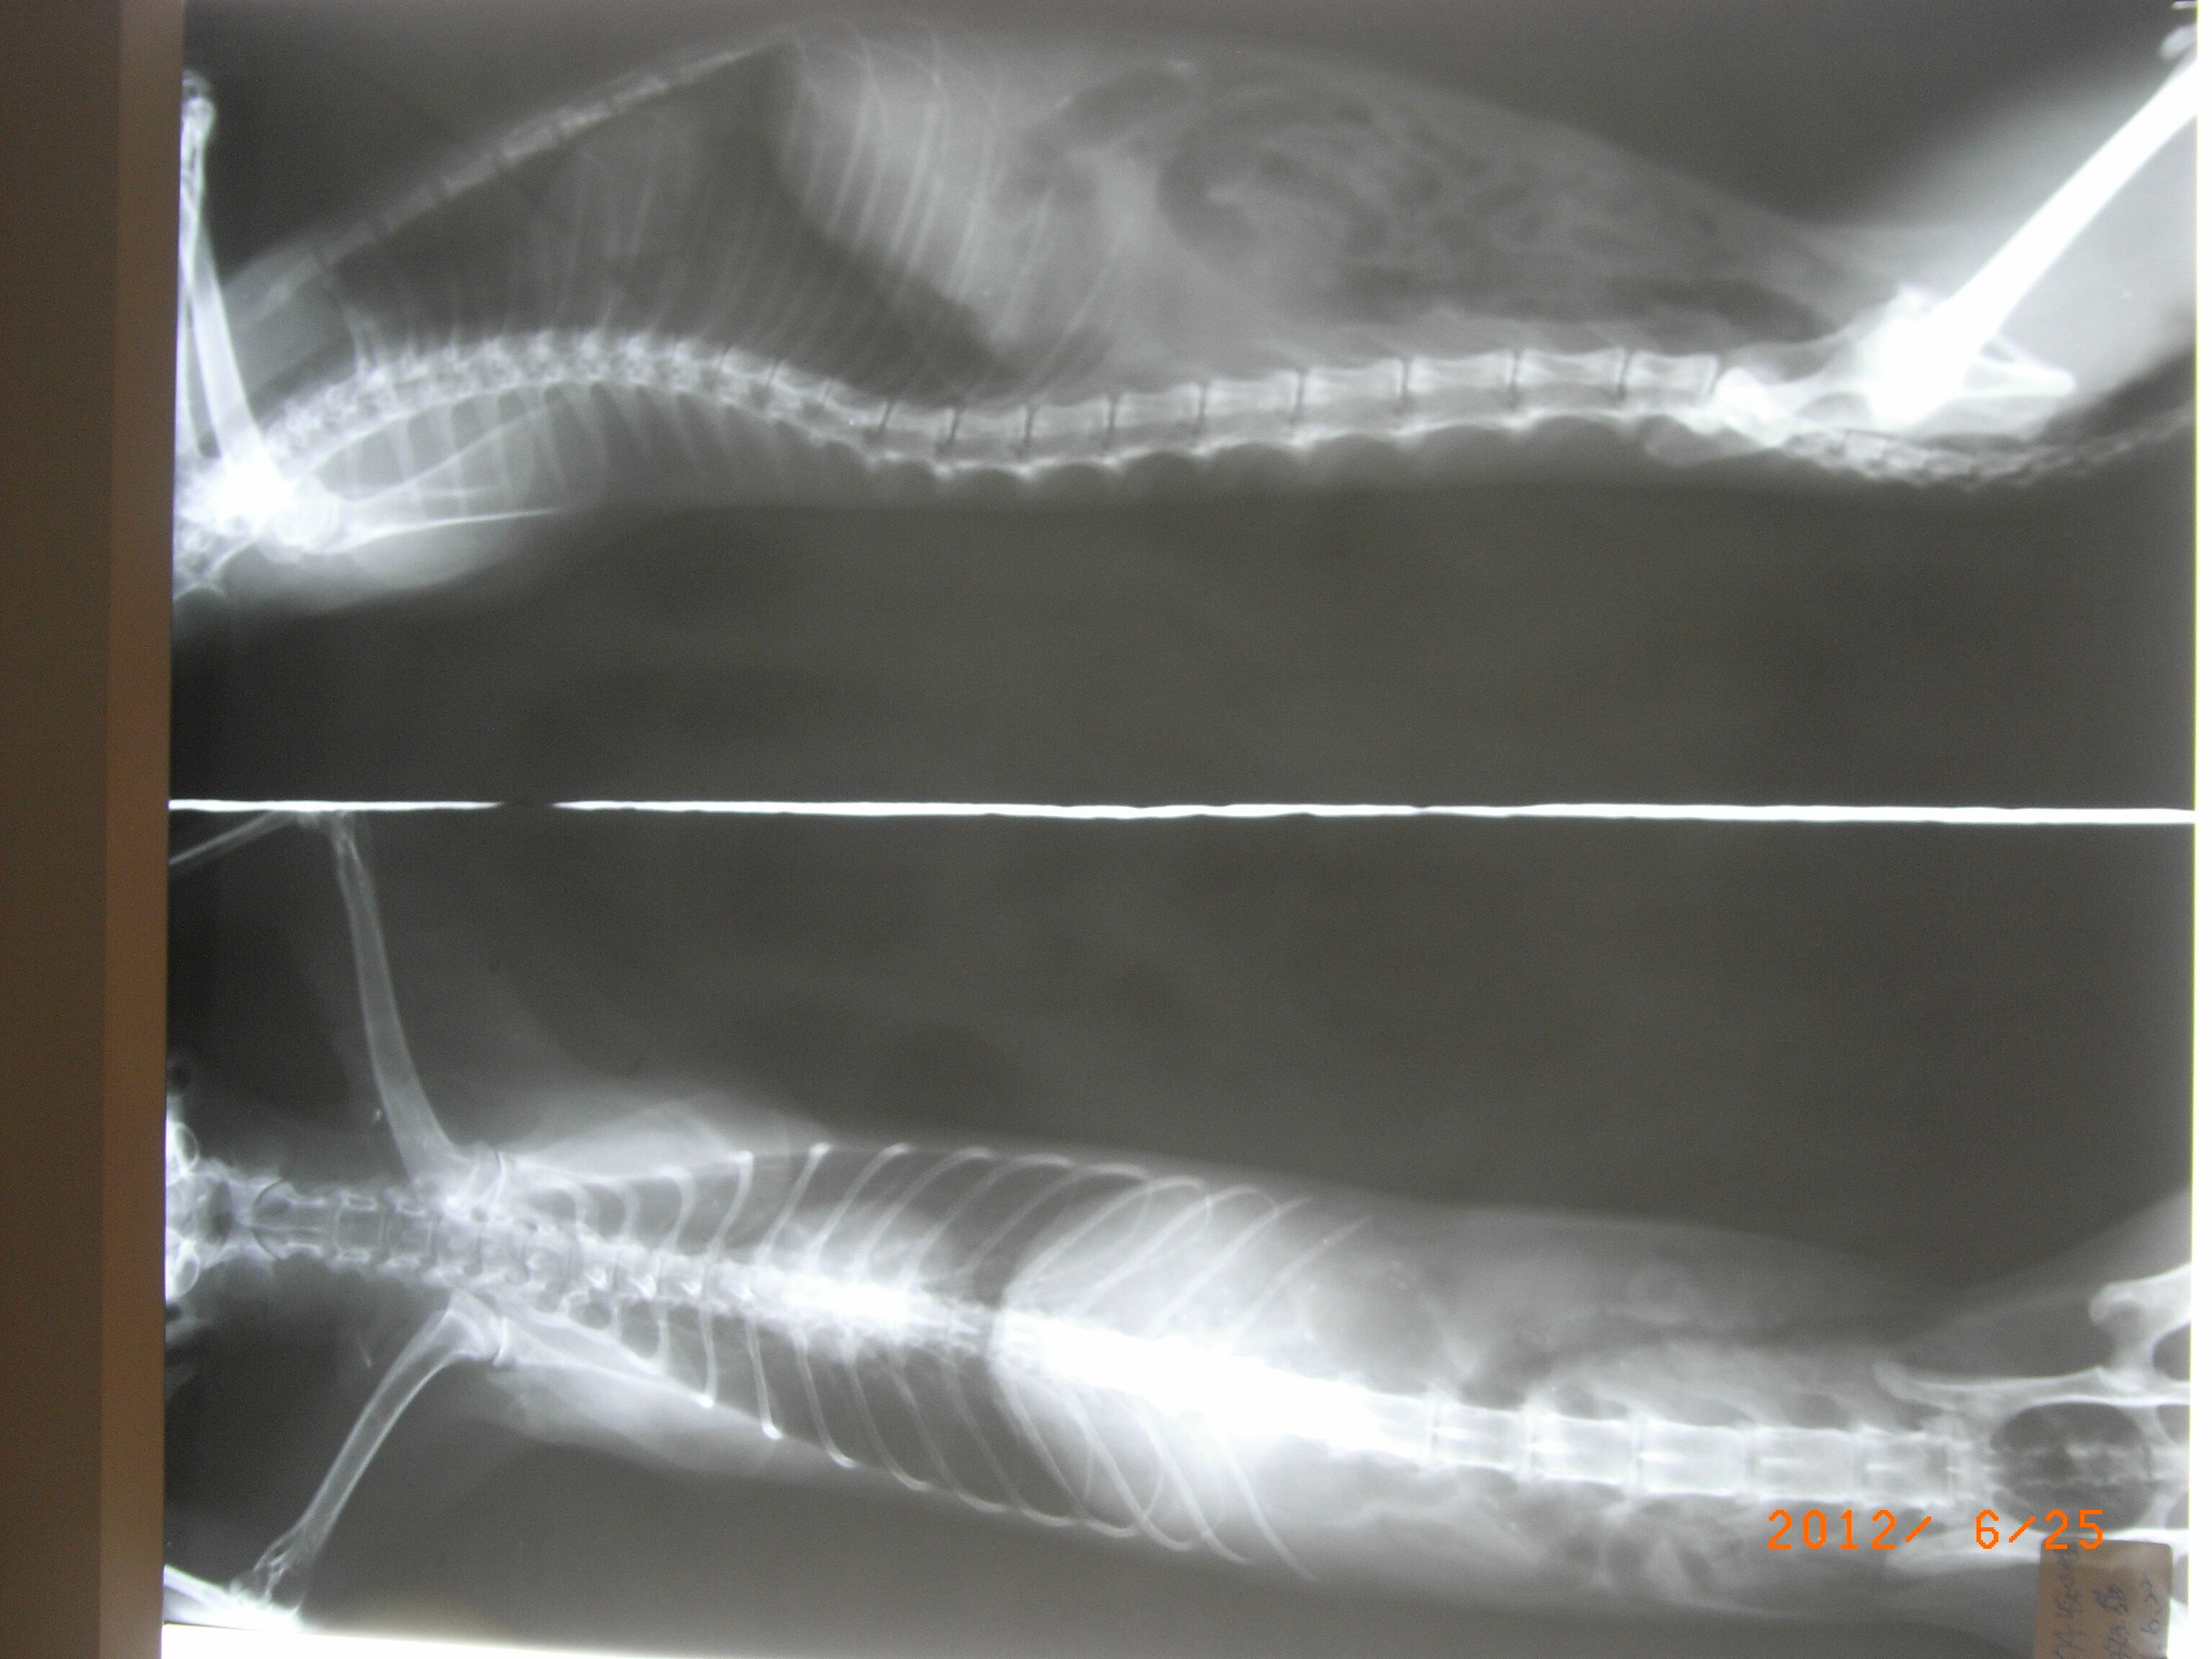

- 編號: 473

主題: 癱軟在路邊的貧血口炎貓 申請者姓名: 徐慕雯 花色: 申請日期: 2012-06-28 03:59:23 申請者部落格: 申請者臉書網址: 所在縣市/合作醫院: 桃園縣/普羅動物醫院 治療費用: 4350元 需求人數: 11人 已結案 (2012-12-01 20:35:46) 報名人員: 姆姆(已付款)、張角倫(已付款)、張角倫(已付款)、老七(已付款)、Alumi Lu(已付款)、sandy_huanglichuan(已付款)、Hitomi Akanishi(已付款)、何偉靖(已付款)、周小蕾(已付款)、FL(已付款)、冥王星獅子(已付款)、 候補人員: 徐慕雯、小舟、 動物病情說明: 這是我原本要TNR的孩子

要誘捕他的那天,發現他癱軟在路邊

送醫檢查後發現貧血、營養不良、口腔潰爛....

有可能因口炎嚴重造成進食不易,倒致貧血....

經牙周病治療、洗牙、服藥.....

已可進食 ~

另,原本要TNR,結果發現這個孩子是已經結紮但未剪耳,還好醫生有注意他是結紮過的孩子,所以在幫他洗牙(麻醉下)順便幫他剪耳 ~ 以免未來被重覆誘捕